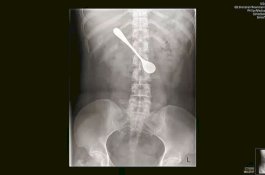

Wanita ini Telan Sendok Saat Mencoba Hilangkan Tulang Ikan di Tenggorokannya